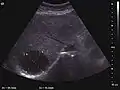

They can be single or multiple, with variable size, generally less than 20 mm (congenital). Rarely, sizes can reach several centimeters, leading up to the substitution of a whole liver lobe (acquired, parasitic). They may be associated with renal cysts; in this case the disease has a hereditary, autosomal dominant transmission (von Hippel Lindau disease).

The ultrasound appearance is a well defined lesion, with very thin, almost unapparent walls, without circulatory signal at Doppler or CEUS investigation. The content is transonic suggesting fluid composition. The presence of membranes, abundant sediment or cysts inside is suggestive for parasitic, hydatid nature. Posterior from the lesion the acoustic enhancement phenomenon is seen, which strengthens the suspicion of fluid mass. They typically displace normal liver vessels but no vascular or biliary invasion occurs.

Liver cyst

Hydatid liver cyst. Diagnostic criteria are the presence of membranes and sediment inside.